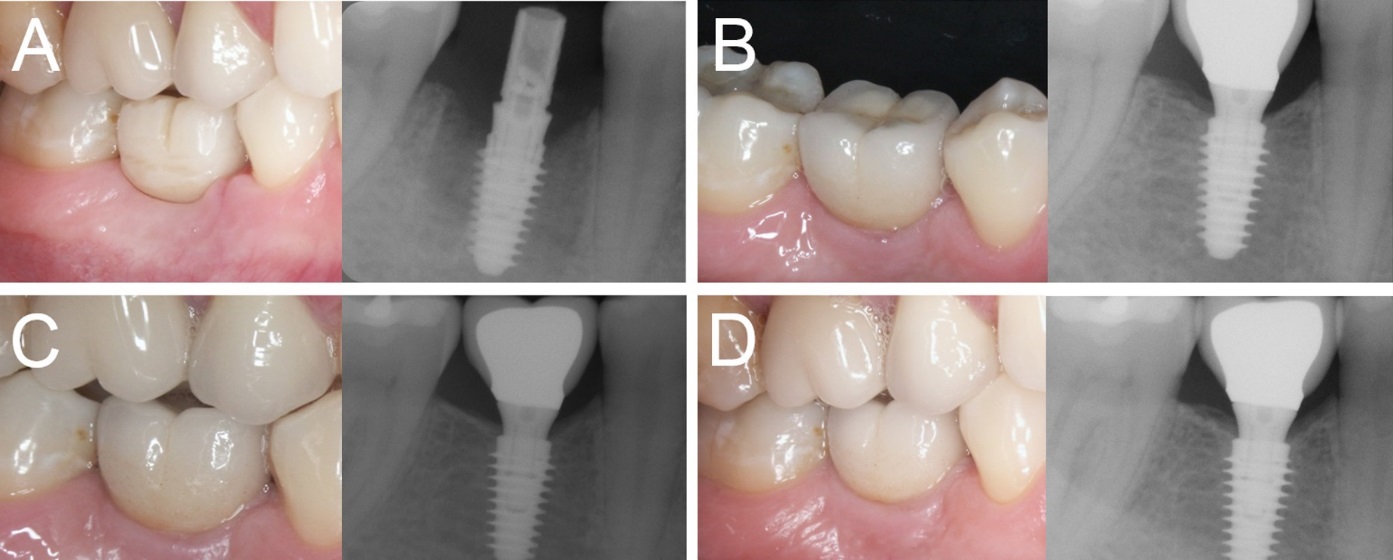

Overall, five patients could not attend the 4-year control visit and were therefore classified as drop-outs, despite the fact that the implants were still in operation. However, 4 years after insertion, only one implant was lost, in the posterior maxilla (second premolar, healed site) of a smoking woman, 48 years old at the time of surgery. The failed implant was 3.5 mm in diameter and 10.0 mm in length and was installed in bone type III. This implant failed during the first healing period, exactly two months after the insertion and immediate functional loading, as it lost stability, in the absence of infection. All the other implants were stable; therefore, the overall 4-year implant survival rate was 97.6% (patient-based, with 40/41 fixture in the survival category) and 98.1% (implant-based, with 51/52 implants in the survival category), respectively (Figures 1-4).

Figure 3.Immediate loading of a first mandibular molar (#46) placed in a healed ridge: (A) The implant is placed and loaded within 48 hours of the surgery; (B) three months later, the final metal-ceramic crown is delivered; (C) the 1-year clinical and radiographic control; (D) the 4-year clinical and radiographic control.